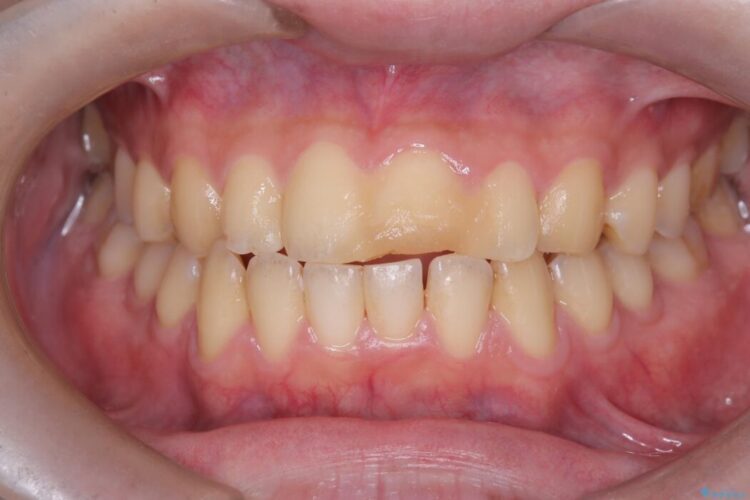

メタルフリー|全ての銀歯をセラミックへ

メタルフリー|全ての銀歯をセラミックへ ビフォー メタルフリー|全ての銀歯をセラミックへ アフター

口腔内の銀歯を全て無くし、白く健康的な状態にしたいとご来院された患者様です。